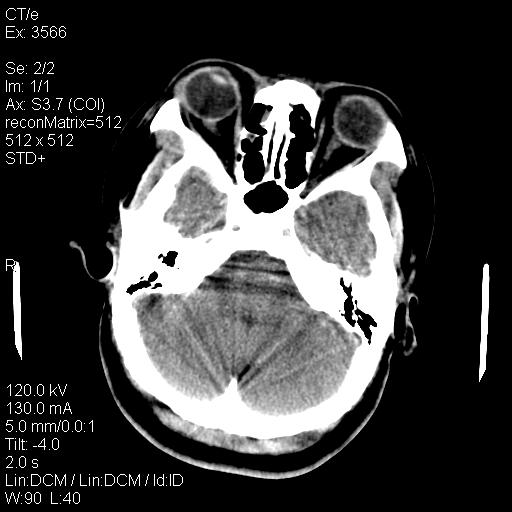

标题: CT9947:女,20岁,妊娠9个月,突然癫痫症状 [打印本页]

标题: CT9947:女,20岁,妊娠9个月,突然癫痫症状

双侧脑白质缺血缺氧性改变,并高度可疑“蛛网膜下腔出血”。

后可复性脑病,

考虑 妊娠子痫或妊高征

双侧脑白质缺血缺氧性改变.

考虑先兆子痫\\子痫致he,建议mri除外有无合并静脉窦血栓形成.

考虑pres

的确应该考虑可逆性后部脑病综合症--pres。感谢天南地北老师的指引,又学了一招儿,开心,呵呵!

考虑可逆性后部脑病综合症